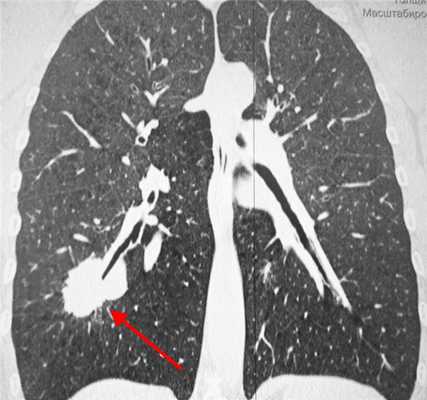

КТ-признаки туберкуломы легкого. Образование диаметром 2 см расположено в правом легком. Отличить туберкулому от рака помогает наличие глыбчатых кальцинатов (извести) в структуре образования, четкие контуры, окружающие фиброзные тяжи, а также мелкие очаги отсева вокруг.

Рентгенография при раке легкого выявляет округлую тень слева. С целью дифференциальной диагностики (отличить рак легкого от туберкуломы, кисты или пневмонии) необходимо выполнять компьютерную томографию — КТ.